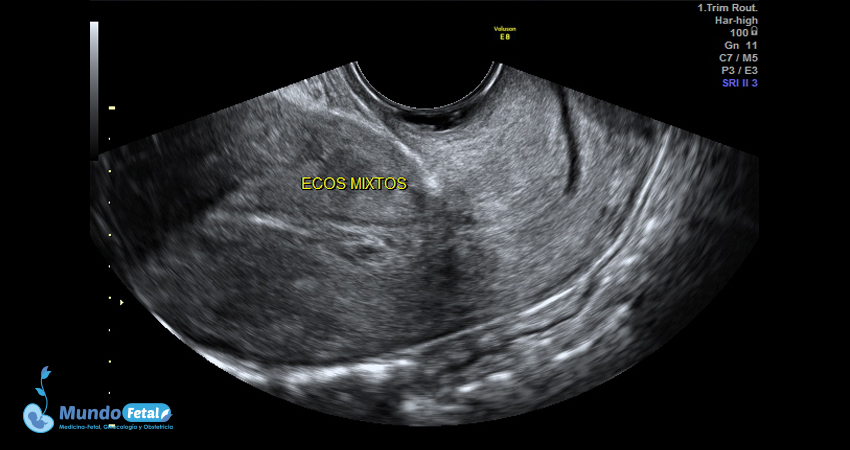

Ultrasonido Pélvico

Estudio anatómico de la región pélvica, que brinda información precisa de (vagina, cérvix, útero, endometrio, trompas de Falopio, ovarios y sus tejidos anexos) de cada uno, descartando alguna complicación de estas estructuras.